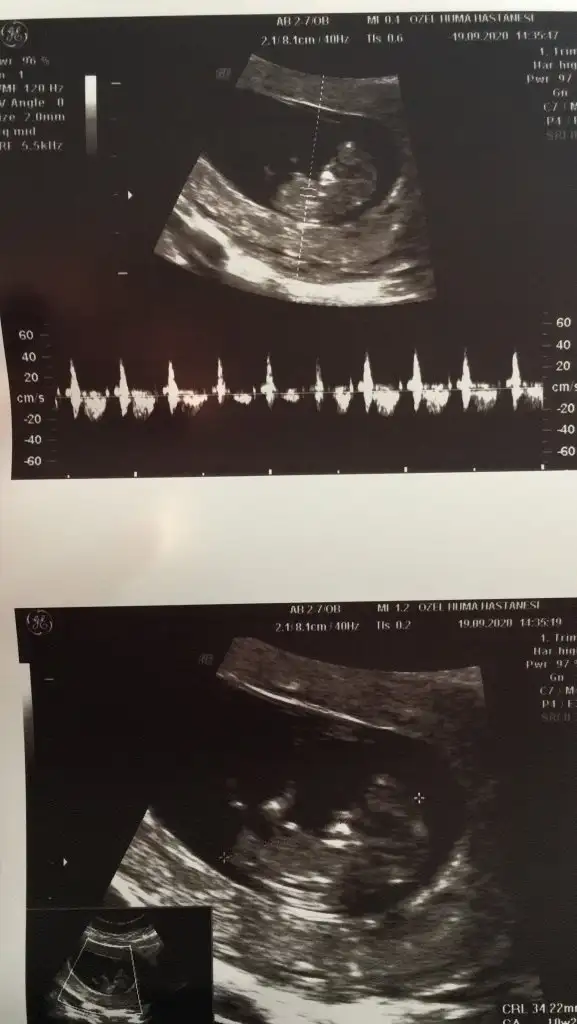

Nub teorisi

Merhaba ikili test görüntüsü varsa daha iyi olur burdan anlaşılmıyor. Tam nuba bakılacak yere doktor işaret koymuş boy ölçmek için. Ya da ben göremiyorum :)

Yani çok da fazla ilgilenmedi doktor.Tayin sebebiyle şehir değiştirdik .Elimde bir de şu şekilde var rica etsem buna bakar mısınız?